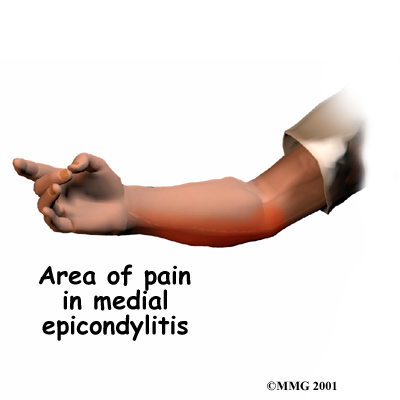

Medial epicondylitis is commonly known as golfer's elbow. This does not mean that only golfers have this condition. But the golf swing is a common cause of medial epicondylitis. Many other repetitive activities can also lead to golfer's elbow: throwing, chopping wood with an ax, running a chain saw, and using many types of hand tools. Any activities that stress the same forearm muscles can cause symptoms of golfer's elbow.

Golfer's elbow causes pain that starts on the inside bump of the elbow, the medial epicondyle. Wrist flexors are the muscles of the forearm that pull the hand forward. The wrist flexors are on the palm side of the forearm. Most of the wrist flexors attach to one main tendon on the medial epicondyle. This tendon is called the common flexor tendon.

The main symptom of golfer's elbow is tenderness and pain at the medial epicondyle of the elbow. Pain usually starts at the medial epicondyle and may spread down the forearm. Bending your wrist, twisting your forearm down, or grasping objects can make the pain worse. You may feel less strength when grasping items or squeezing your hand into a fist.